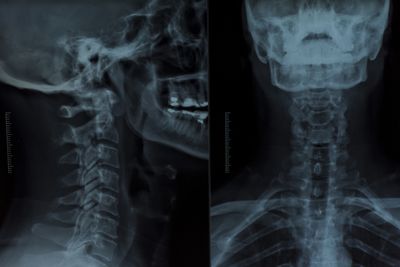

Рентген головы и шеи

Рентген головы и шеи в Екатеринбурге .jpeg

Рентген головы

Рентген черепа позволяет исследовать кости свода и основания черепа, кости лицевого скелета и головного мозга. Рентгенологическое исследование головы помогает поставить диагноз, решить вопрос с выбором тактики лечения и проконтролировать динамику лечебного воздействия.

Рентгенологическое исследование головы может проходить в одной или нескольких проекциях: правой боковой, левой боковой, переднезадней, заднепередней, аксиальной, полуаксиальной, прицельной.

Рентген шейного отдела позвоночника

Шейный отдел – один из самых уязвимых отделов позвоночника.